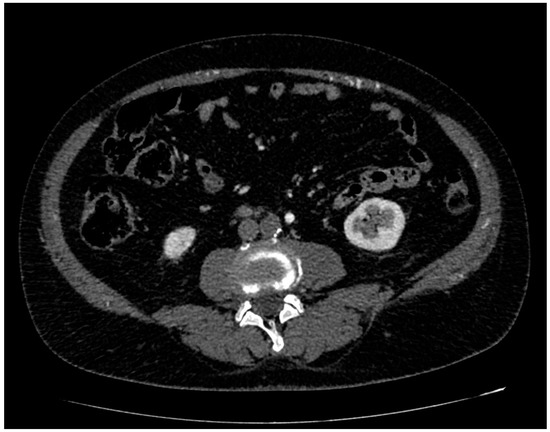

| 9/11 | Subrenal aorta to common iliac arteries bilaterally | 81.8% |

| 2/11 | Infrarenal aorta to common iliac arteries bilaterally | 18.2% |